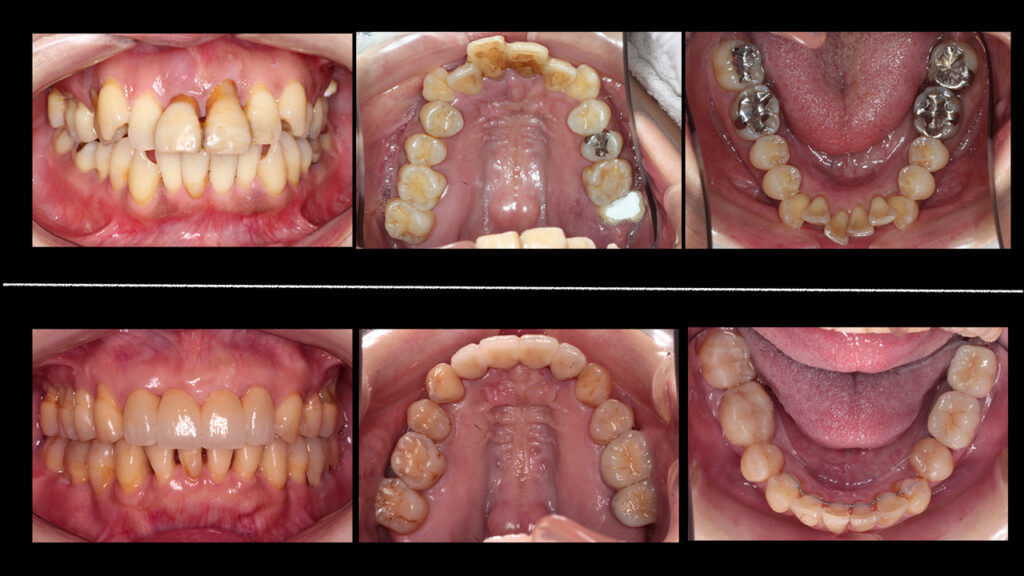

実際の治療例をご紹介します

症例1: 他院で抜歯と診断された重度歯周病を改善

患者様 60代男性

主訴 歯がグラグラして噛めない

他院での診断 全顎抜歯・総入れ歯

当院での治療 ・歯周病治療

・歯周組織再生療法

・部分的なインプラント治療

結果 8本の歯を保存することができ、しっかりと噛めるようになりました。

治療期間:10ヶ月

治療費:約90万円(保険適用部分含む)

症例1

患者様 40代女性

主訴 噛みにくい、全体的に治したい

当院での治療 ・歯周病治療(歯周組織再生療法含む)

・矯正治療

・インプラント

・口腔機能回復治療(ブリッジを含む補綴全般)

結果 自然で美しい歯になり、自信を持って笑えるようになりました。

治療期間:4年

治療費:約440万円